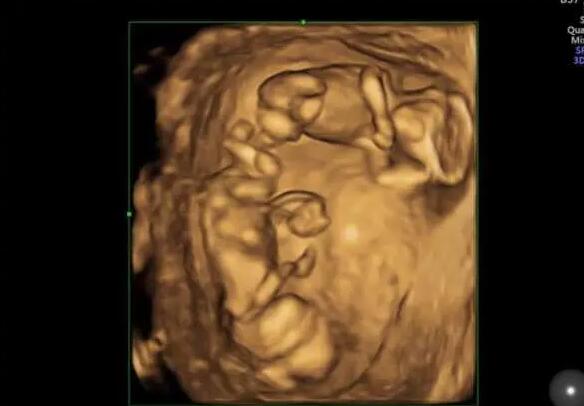

可能很多人都不知道,降调的作用是什么,其目的是为了控制垂体功能,让卵巢处于安静的状态中,为促排卵和取卵做好充足的准备。在做好充分准备的情况下,才能顺利进入到促排卵阶段。